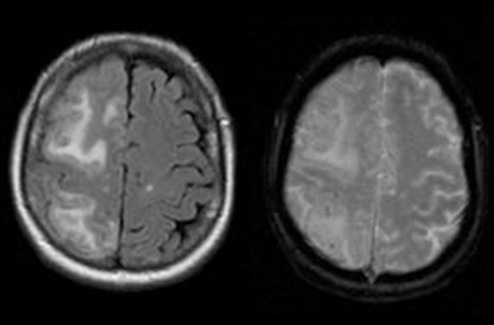

- Double-Contrast MRI Technique Identifies Small Tumors